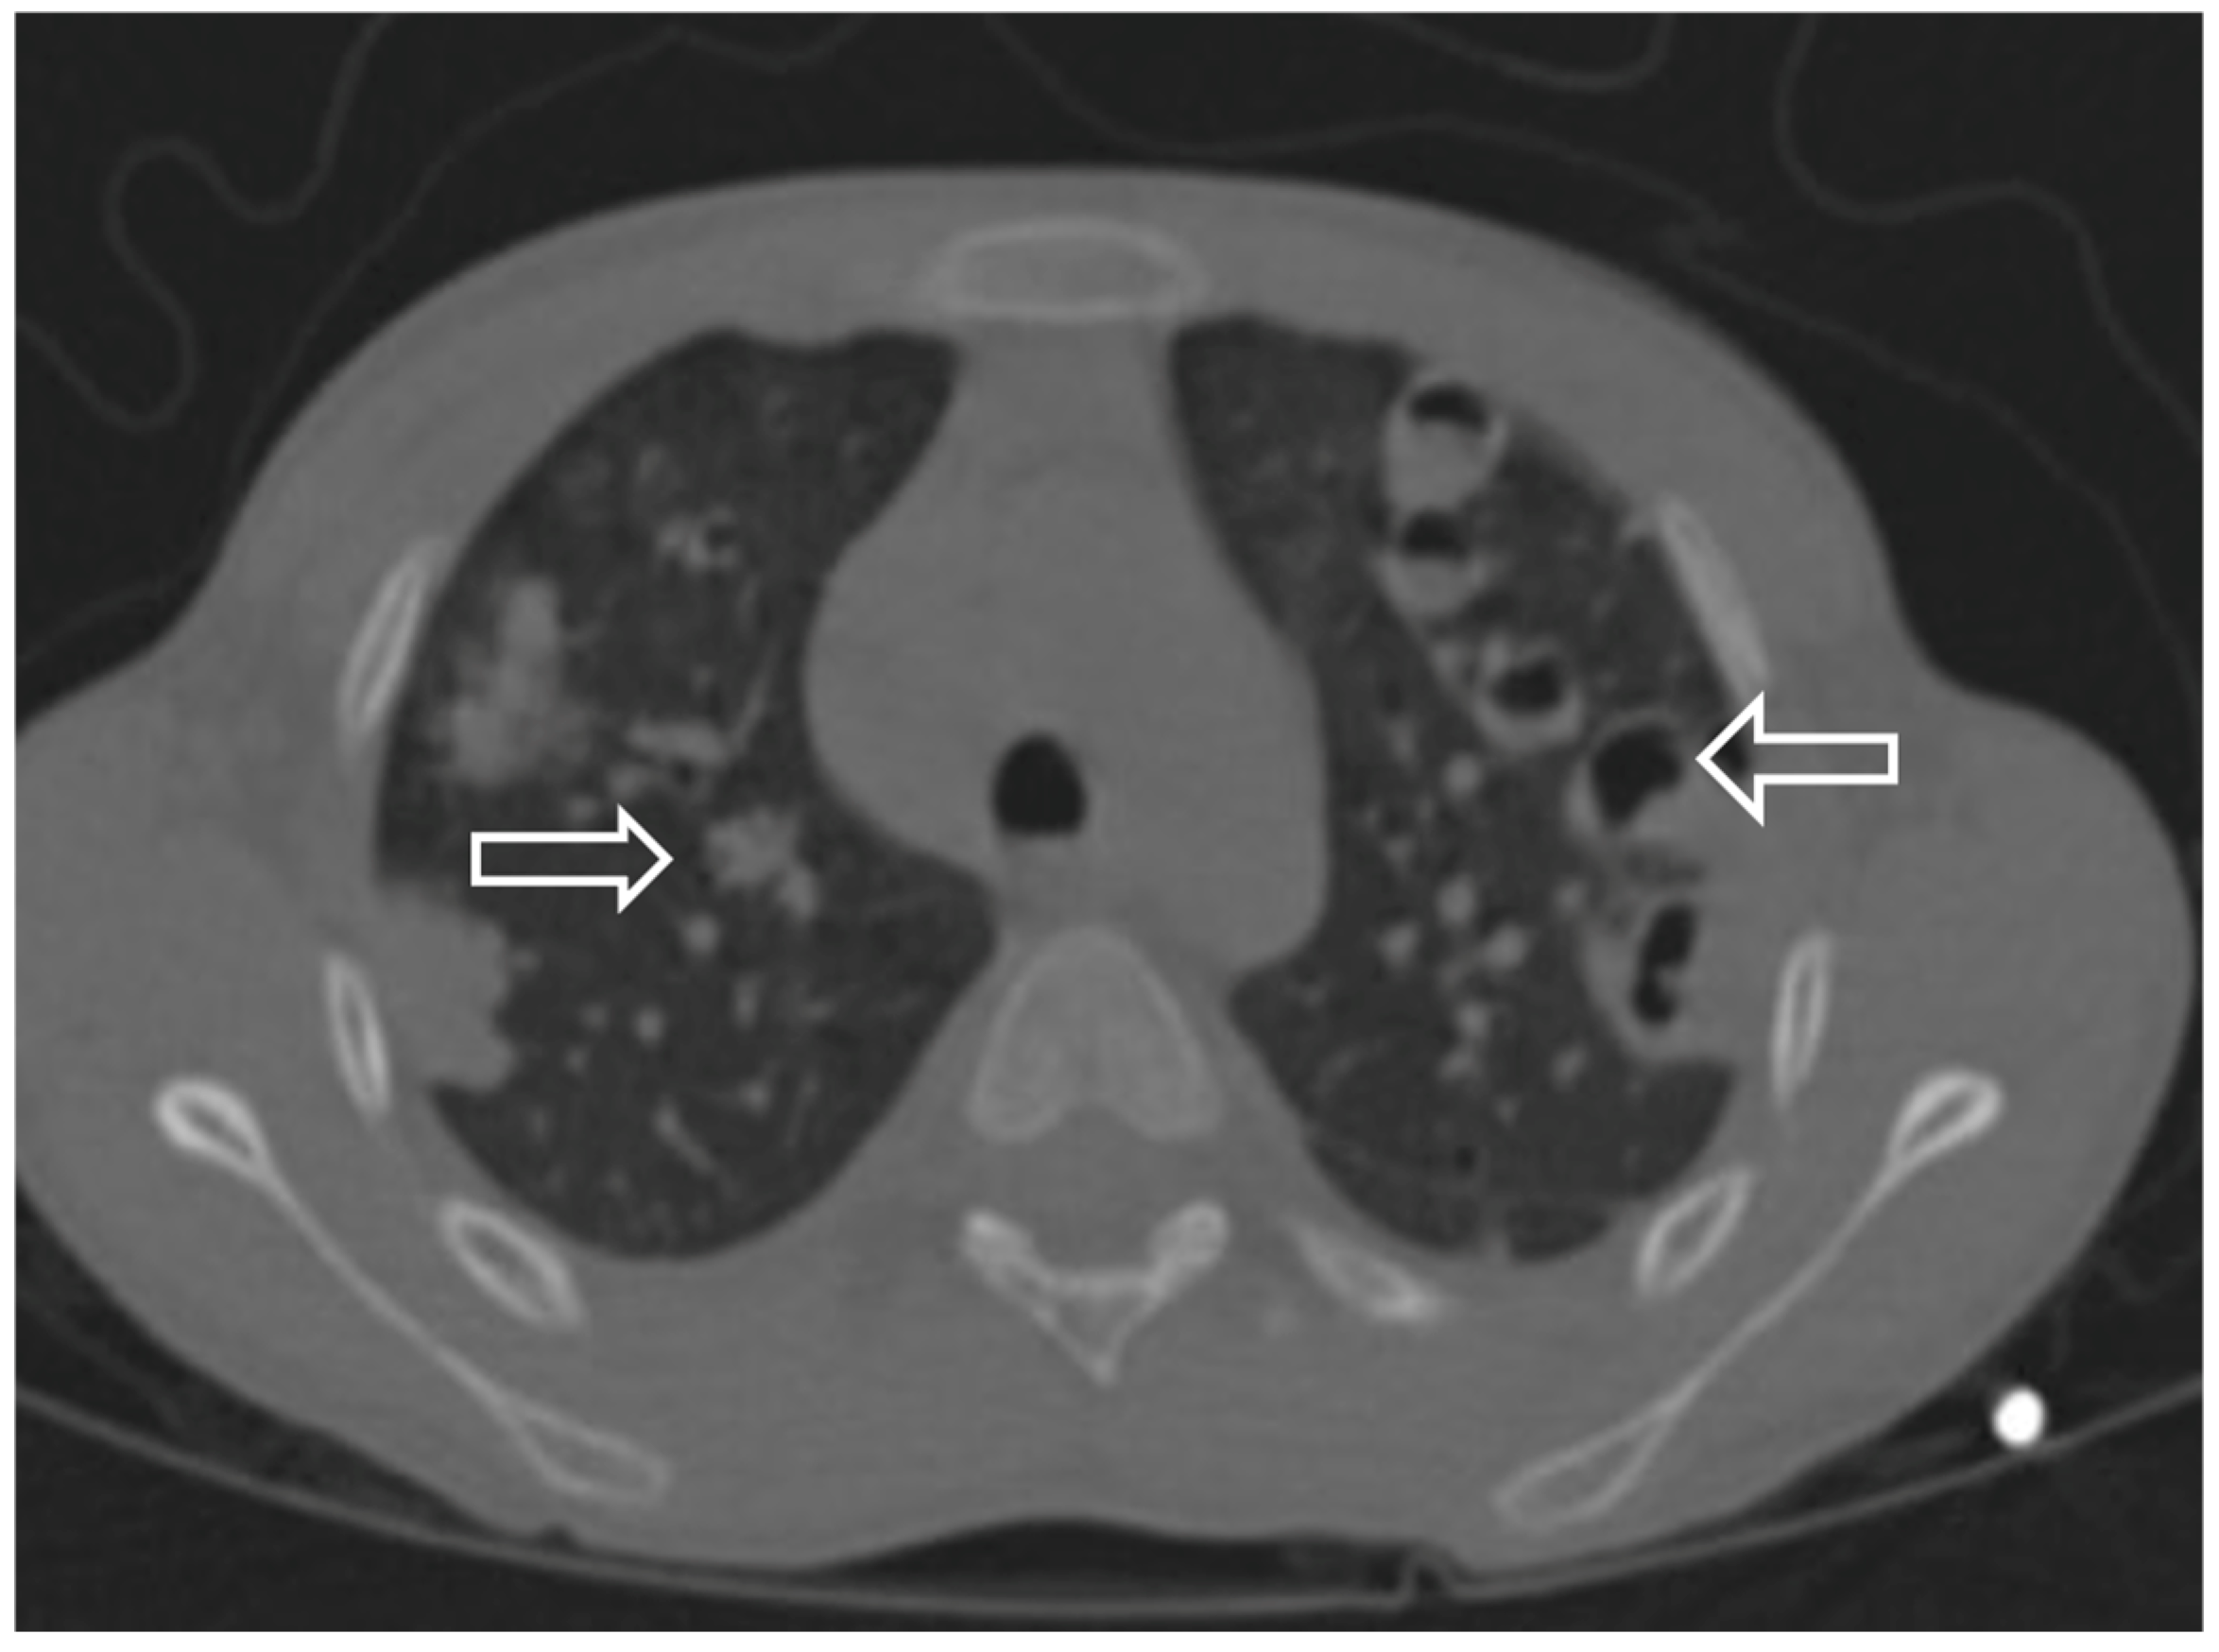

| CT | Effusion | Nodul Cavitation Reverse halo Pneumothorax | Nodul Cavitation Reverse halo | Nodul Ground glass opacity | Nodul Cavitation Reverse halo sign |